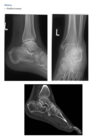

Foot pain

A lateral radiograph of the left foot demonstrates a prominent talar beak

­ (arrow) and bony sclerosis overlying the middle

facet (arrowheads). Coronal CT through the middle

facet shows talocalcaneal fusion, with bony bridging between the talus and the sustentaculum tali of the

calcaneus

Diagnosis: Tarsal coalition

abnormal fusion

of one or more of the tarsal bones, may be fibrous,

cartilaginous, or osseous and may be posttraumatic, or congenital.

Most

common tarsal coalitions are calcaneonavicular and

talocalcaneal.

Radiographically, calcaneonavicular coalition may

be suspected because of elongation of the anterior

facet of the calcaneus on radiographs (i.e., anteater

sign. CT can also be used to confirm coalition and shows

­ sclerosis at the articulation

Congenital coalition usually evolves from fibrous to osseous

coalition and may not be apparent on the initial

evaluation

Talocalcaneal coalition can result in dorsal beaking

of the talar head (Fig. 2.3.6, arrowhead), the so-called

C-sign (arrows)